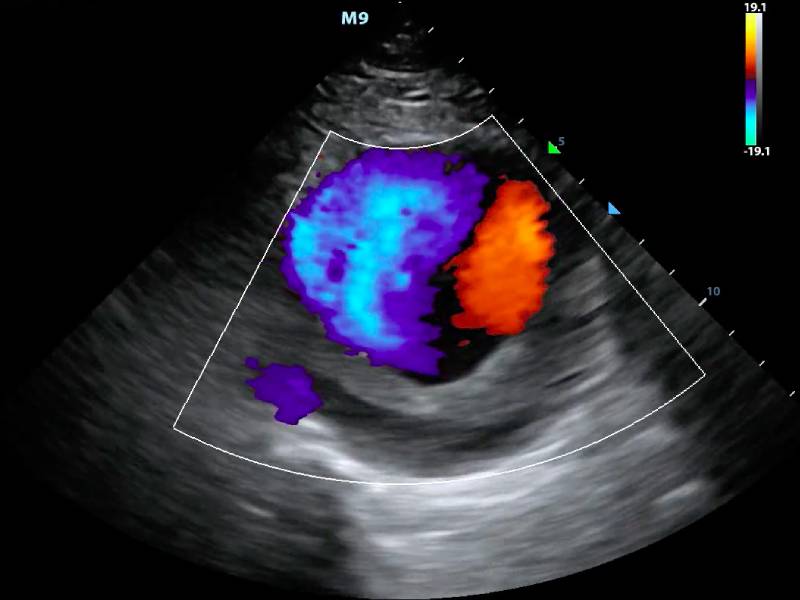

Colour Doppler imaging is a non-invasive test that uses sound waves to visualize blood flow in the body. It is particularly useful for diagnosing issues related to blood vessels and heart conditions. Meera's doctor suspected that her symptoms might be related to poor circulation, and the Colour Doppler scan was the ideal tool to investigate further.

The Colour Doppler imaging had revealed a significant blockage in one of Meera's leg veins. This was causing the swelling and fatigue that had been plaguing her. With this clear diagnosis, her doctor could recommend an effective treatment plan, which included medication and lifestyle adjustments. Meera was relieved to finally have answers and a path forward.

For healthcare providers, incorporating Colour Doppler imaging into their diagnostic repertoire can significantly enhance patient outcomes. It provides a clear, visual representation of blood flow, making it easier to pinpoint issues and tailor treatment plans accordingly. This efficiency not only benefits patients but also optimizes the workflow of healthcare facilities.